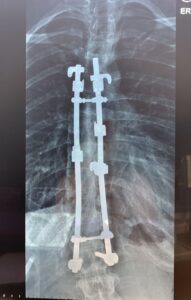

After days of digesting and processing the news, I realized that I had no option. My Scoliosis was progressing at a rapid rate, and therefore without surgery, my life expectancy would have been around 30 years. So in 1994, age 14, I underwent a Scoliosis spinal fusion to have two stainless steel Harrington Rods attached to my spine from L1 to around T5.

I’m not going to lie, the road from then to now has been extremely challenging at times. Living with Scoliosis is a daily battle. Some weeks my pain levels are minimal and others are chronic. I often remind myself that the surgery my doctors performed was lifesaving. For that I am forever grateful. Without their amazing work I would not be here today, married to the love of my life and raising my two beautiful children.